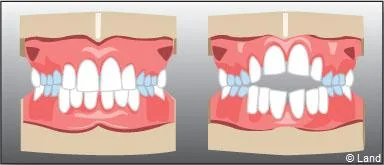

La succion d’un doigt ou de tout autre objet doit être arrêtée au plus tard avant 5 ans, c’est-à-dire avant l’évolution des incisives définitives.

Lorsque des dents de lait ont été extraites trop tôt parce qu’elles étaient cariées, les dents de part et d’autre peuvent migrer et combler l’espace, bloquant ainsi l’éruption des dents définitives. Il est alors nécessaire de maintenir cet espace avec un appareillage spécifique appelé « mainteneur d’espace » jusqu’à l’évolution des dents définitives.

De plus, il est opportun de corriger très tôt certaines malpositions. Les appareils généralement utilisés sont amovibles avec une armature en résine, mais peuvent aussi être fixes à l’aide de bagues sur les premières molaires définitives.. Suivant leurs conceptions et la manière dont ils sont portés, ils auront une action sur la position des dents mais aussi sur la croissance.